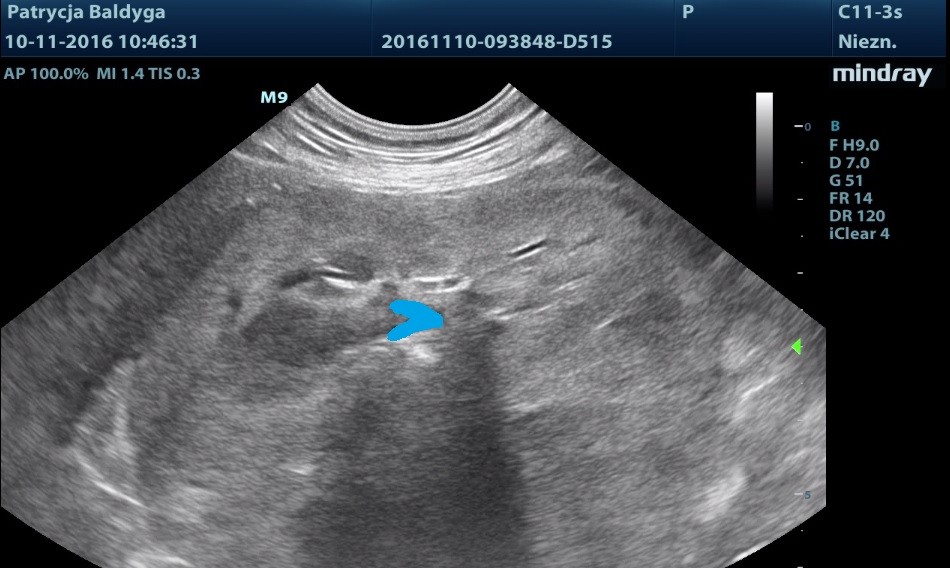

Po dokładnym przeskanowaniu zmiany w różnych przekrojach wyraźnie widać, że jej pochodzenie jest nerkowe, obraz sugeruje duży guz nerki. Na niebiesko zaznaczona nieznacznie, do ok. 3 mm poszerzona miedniczka nerkowa, patrz: film i zdjęcie 2.